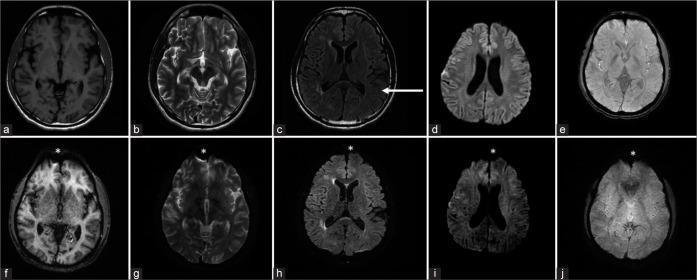

This was a retrospective observational study of 50 patients, who could benefit from faster MRI brain scans. The T1, T2, fluid attenuated inversion recovery, diffusion-weighted imaging (DWI), and T2*/susceptibility-weighted imaging sequences were acquired, conventionally and with EPIMix. Conventional and EPIMix images were assessed by two radiologists for overall quality, motion, and susceptibility artifacts and scored on a Likert scale. The scores given for conventional and EPIMix images were compared. The diagnostic performance of EPIMix was also assessed by the ability to detect clinically relevant findings.

The acquisition time for conventional MRI was 11 min and 45 s and for EPIMix 1 min and 15 s. All EPIMix images were sufficient for diagnostic use. On assessment of the diagnostic performance, it was excellent for ischemic and hemorrhagic strokes. Smaller lesions, lesions adjacent to bone, and post-operative tumors were difficult to identify. Moderate to perfect agreement (Kappa values 0.41-1) was seen between radiologists for all categories except skull base, calvarial, and orbital lesions. Image quality, artifact assessment showed excellent interobserver agreement (>90%) for the scores. All EPIMix images showed reduced motion artifacts. The EPIMix-DWI was comparable to conventional-DWI in terms of quality and artifacts. The remaining sequences showed reduced quality and increased susceptibility.